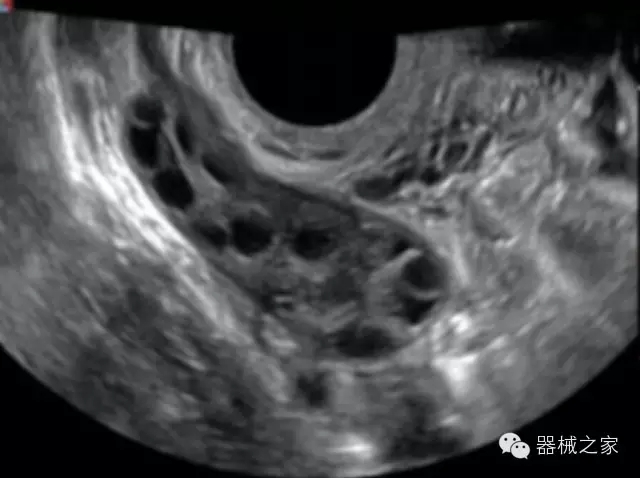

臨床圖片賞析

·完整的3D/4D臨床應(yīng)用,STIC, MCUT 和Auto NT等滿足產(chǎn)科所有應(yīng)用;

·更高的HQ羊膜腔鏡成像技術(shù)精細(xì)觀察每一個(gè)暗區(qū)細(xì)節(jié);